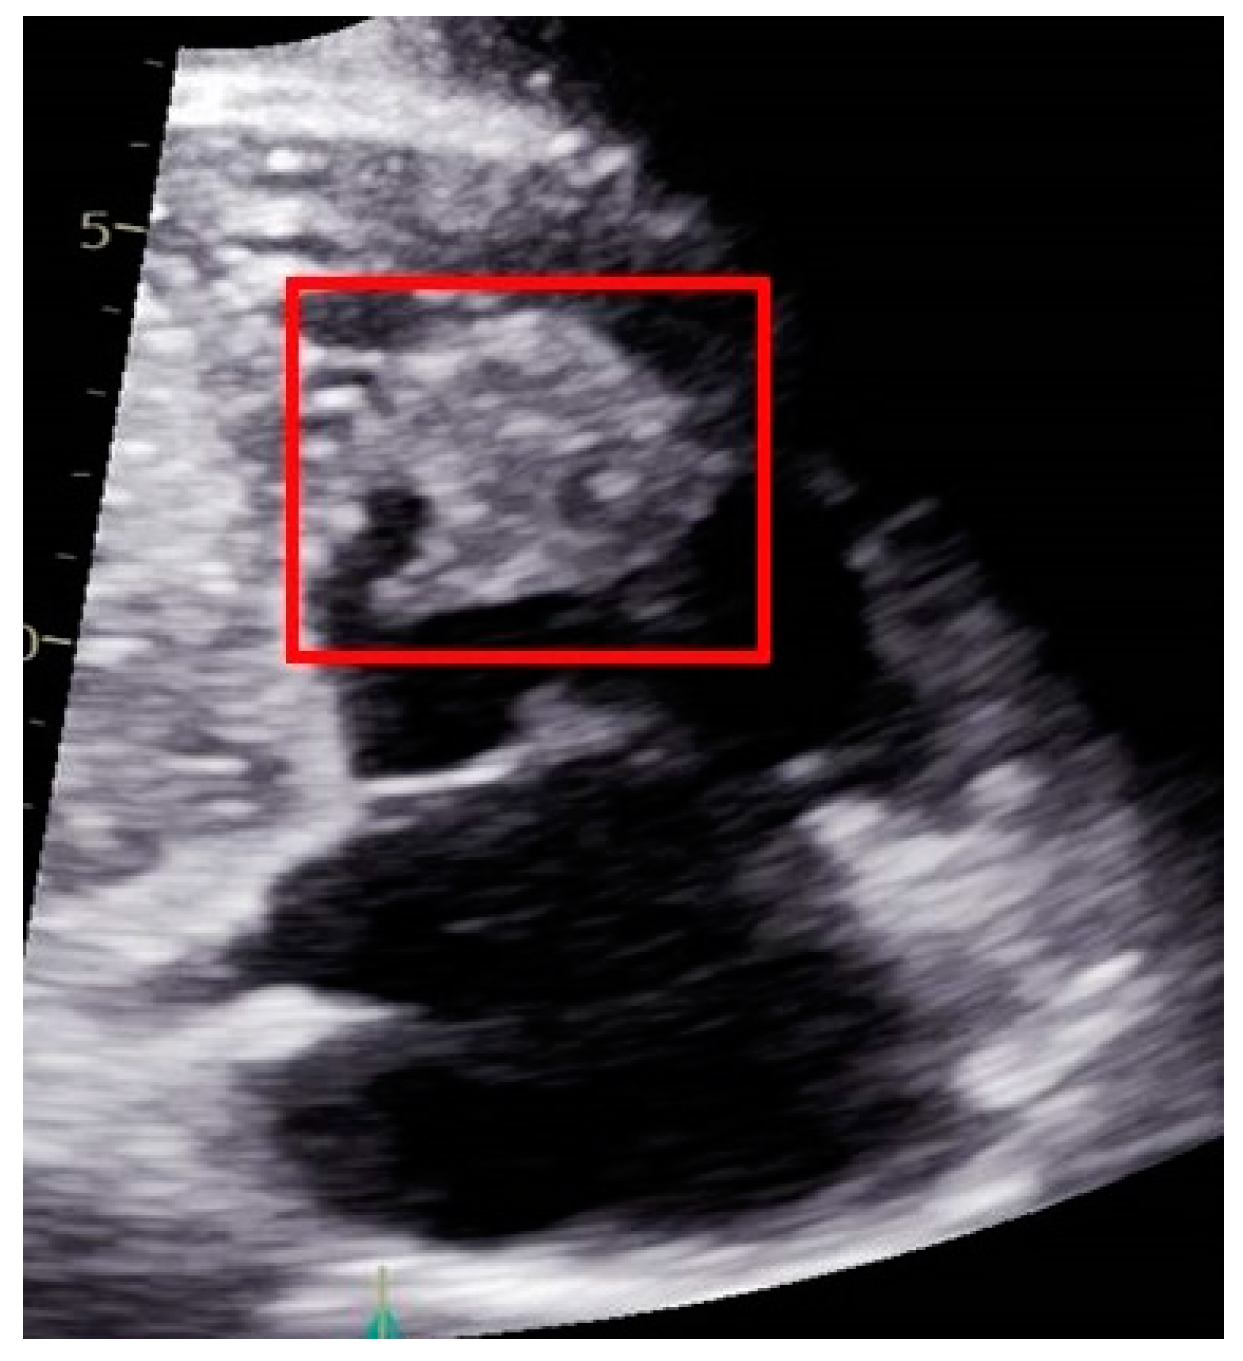

2.3. A Male with Pancreatic Cancer Metastasized to the Right Ventricle of the Heart

| 3 | 63 | M | Pancreatic Adenocarcinoma | Heart | PET-CT Histopathology | FOLFIRINOX |